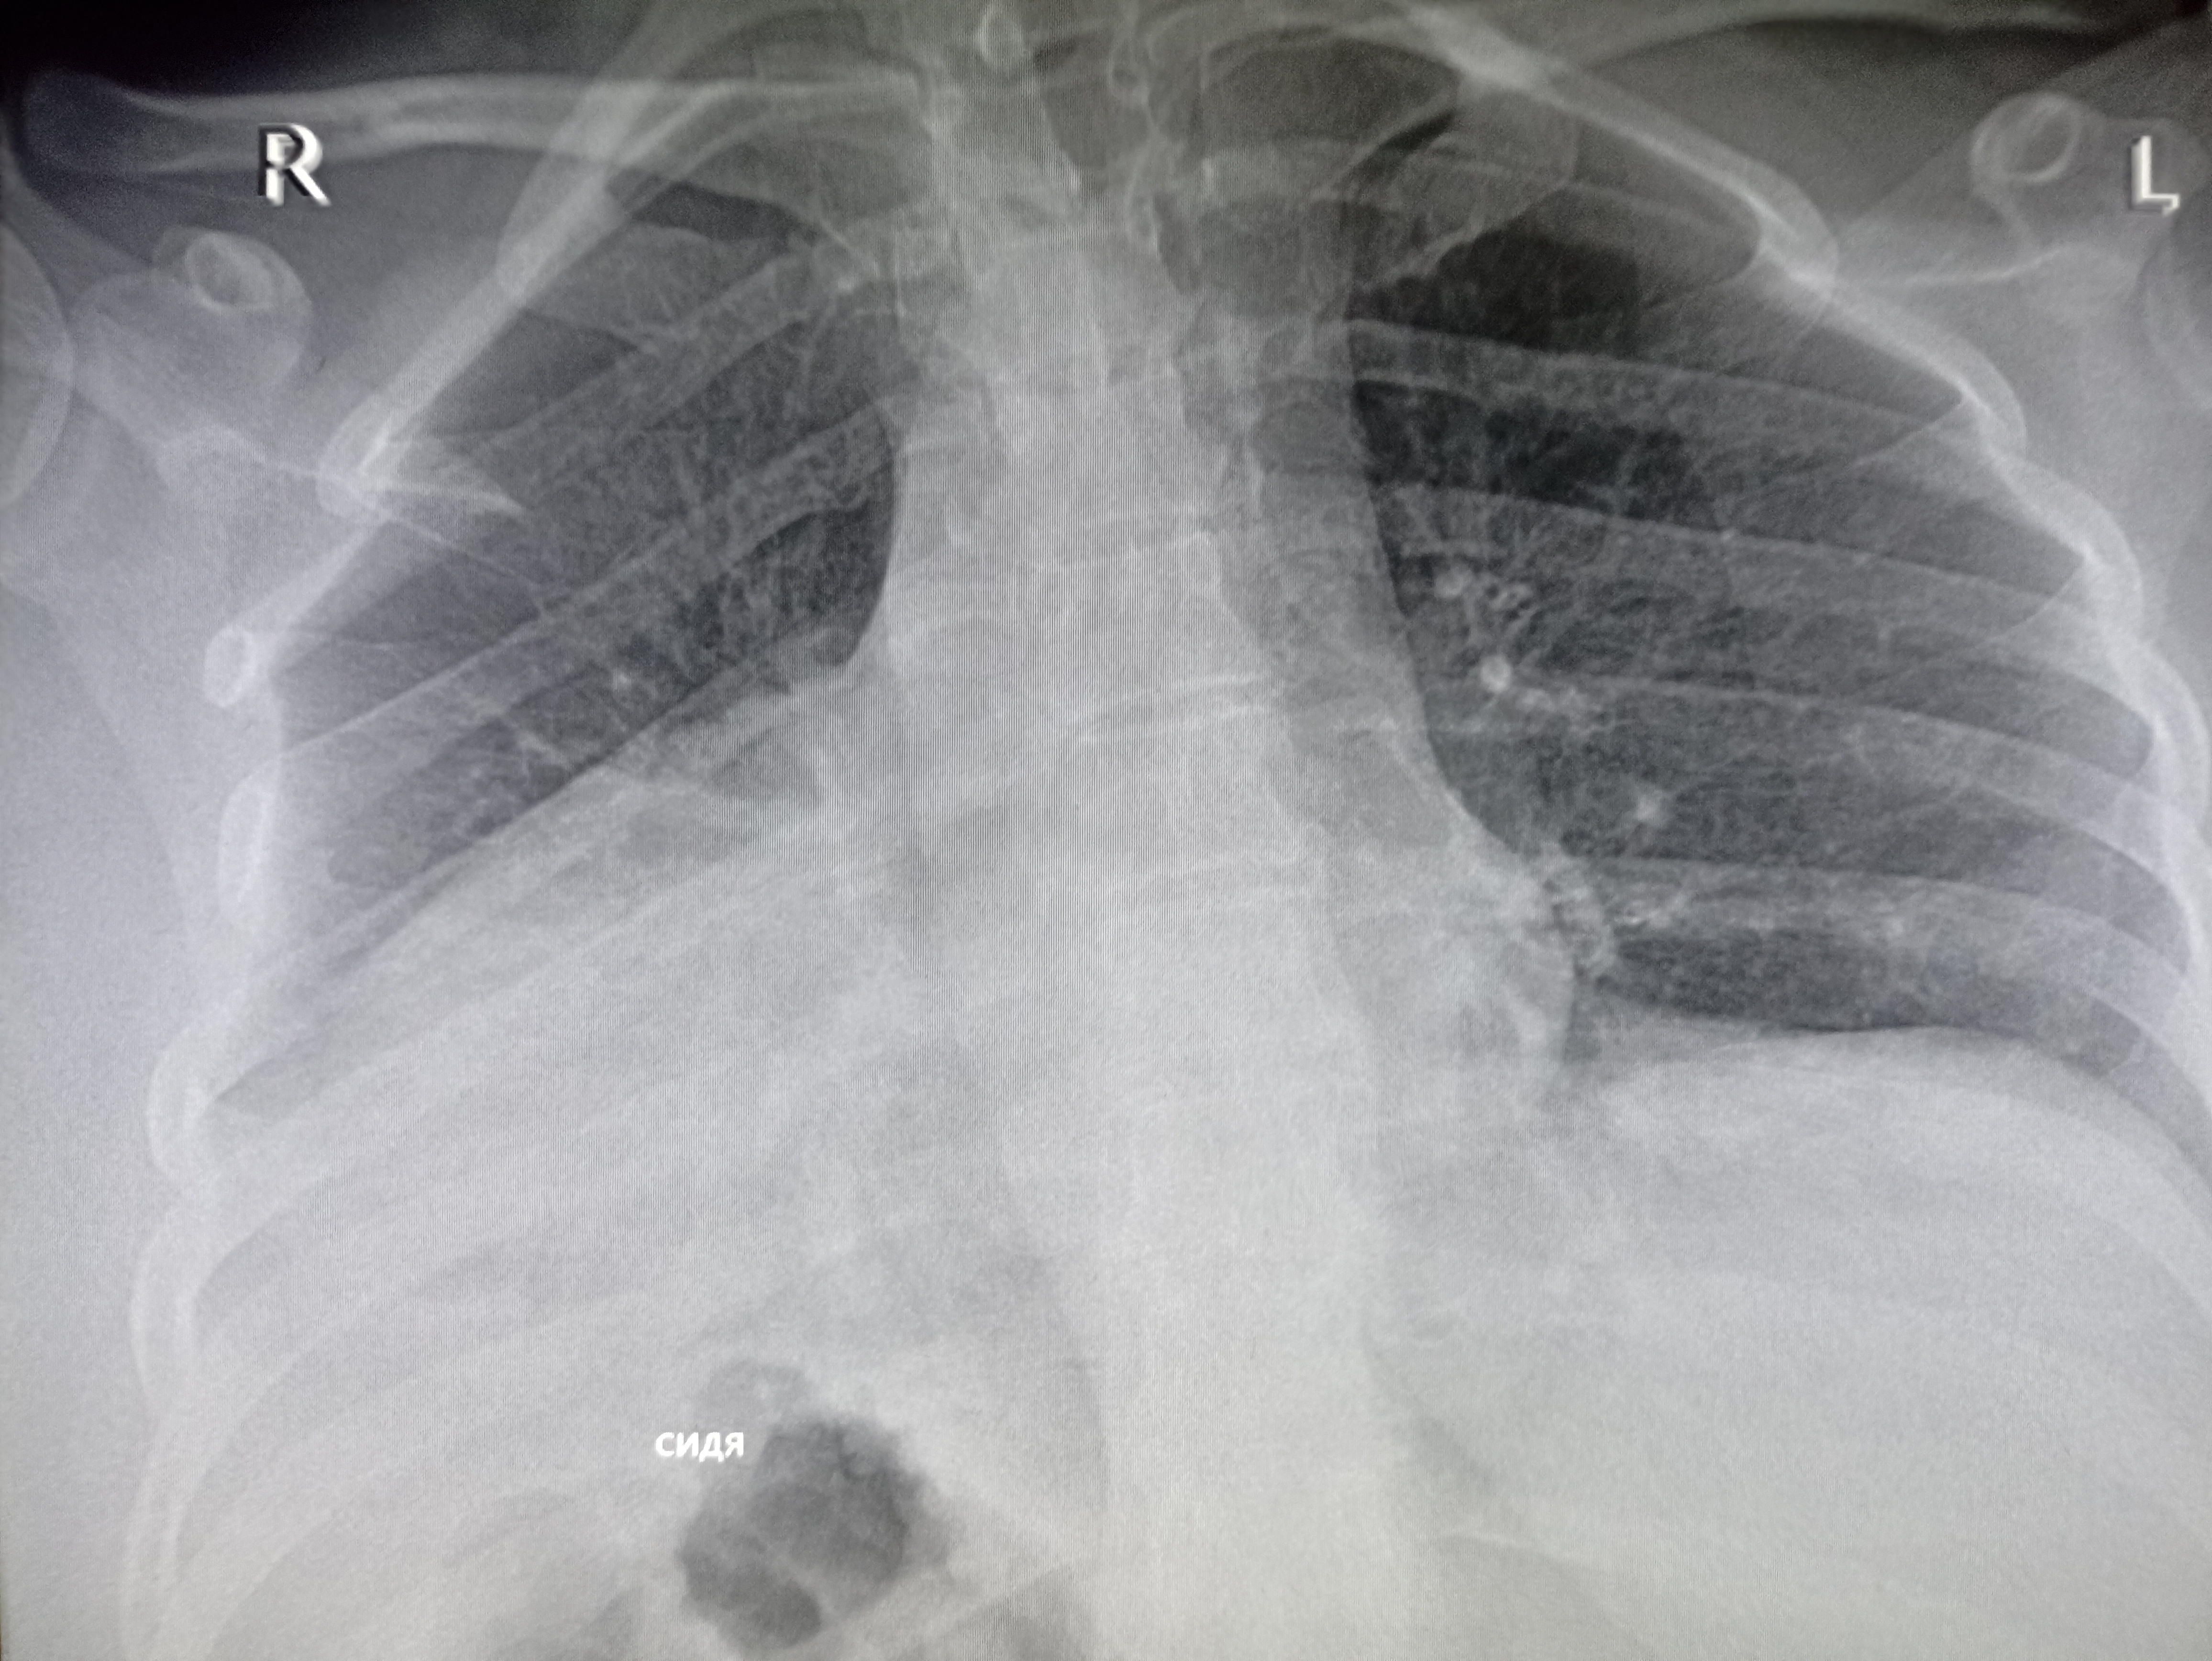

Здравствуй двачик, сегодня мы с вами опять будем играть в рентгенолога, я вам буду постировать фоточ

Здравствуй двачик, сегодня мы с вами опять будем играть в рентгенолога, я вам буду постировать фоточки, а вы узнавать пиздецомы на них.

А пока мы обсуждаем этот сложный вопрос я вам фоочки буду показывать! Штош погнали!

На первых двух картинках один и тот же чел по видимому. На 3ей определенно какие то узлы еаные есть

Пневмония в нижнем сегменте.

Ну или тубер

>>327475007

Там еще жижа и плеврит

>>327475010

Бля пиздец фу гадость. Он уже лежит где-то или на своих двоих прищел?

Дренаж?

>>327475034

Пунктировали два раза уже. Приехал из поликлиники в приемник. Он там всяким по вене ставился и у него него не ток в легких все фу неоч.

Гидроторакс с линией демуазо?

Ну чот, а метастазы чому игноришь?

>>327474857

Бля то ли субтотальная пневмония, то ли осумкованный плеврит такой. всё нахуй забыл уже с рентгенологии

Тут просто гидроторакс, там недостаточность по большому кругу

Хм, так понимаю увеличены сердце и магистральные сосуды, которые дают такую мощную тень?